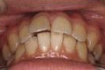

CASE1

前歯の歯並びが悪いのが一番気になります。

右側では良く噛めません↓(16歳/女性)

||||||||

概要・担当医コメント:叢生・右側咀嚼障害↑

マルチブラケット装置/動的治療期間26ヶ月(23回)

/費用概算:60万円

高校の部活も矯正も両方頑張れたそうです。

上顎右側の小臼歯を1本のみ抜歯させていただき,あとは上下の歯列アーチ形態の修正にて矯正できました。